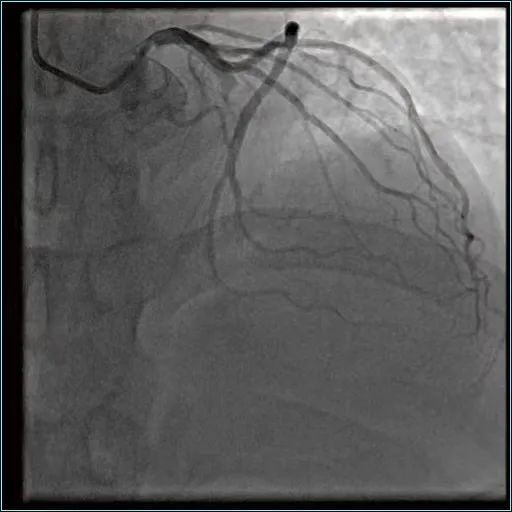

手术后

但是,刘先生除颤恢复心跳以后,非常烦躁不安、极不配合。而心脏手术精度极高,需要在一、两毫米的精细度上去操作。于是,麻醉科紧急麻醉、气管插管,送到导管室进行介入手术。心内科主任说:“如果血管闭塞超过半个小时,心肌就会出现大面积坏死,如果超过两到三个小时,心肌坏死大概要达到60%-70%,所以时间就是心肌、时间就是生命。一进入导管室,我们速度很快,大概10分钟就把血管打通了。”